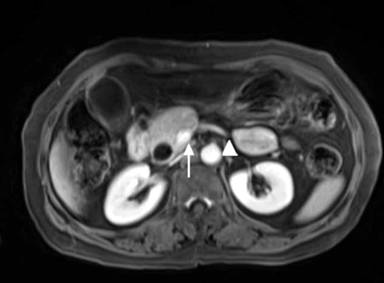

An USG abdomen showed mild hepatomegaly with extrahepatic biliary dilatation and periampullary mass. MRI and MRCP abdomen revealed dilated intra and extra hepatic bile ducts with narrowing of distal CBD with periampullary mass (Figures 1 and 2). MRI abdomen also showed hypoplasia of body and tail of the pancreas suggestive of agenesis of dorsal pancreas (Figure 2). ERCP was done and put biliary stent.

Figure 2. T1FS CEMRI abdomen showing agenesis of the dorsal pancreas. A prominent pancreatic head (arrow) with dilated common bile duct and pancreatic tissue does not extend to the left of the superior mesenteric vein (arrow head). |